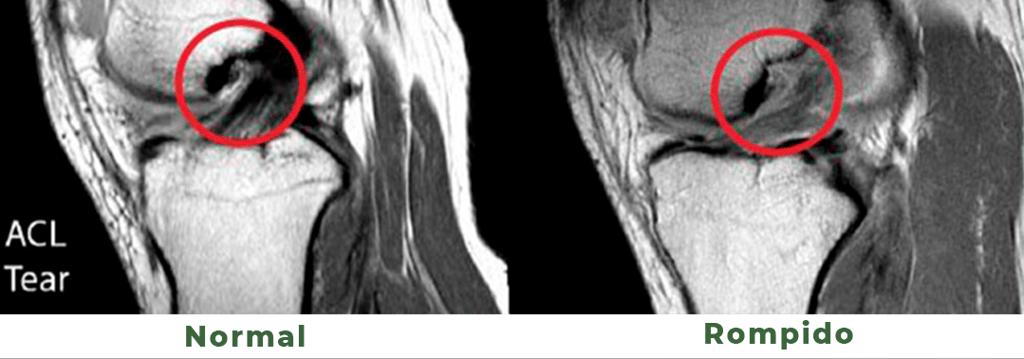

O ligamento cruzado anterior é uma estrutura formada por fibras de colágeno que liga a tíbia (osso da perna) ao fêmur (osso da coxa). A função deste ligamento é manter a união destes dois ossos formando contribuindo para formar a articulação do joelho. O LCA é principal restritor da anteriorização da tíbia em relação ao fêmur, além de ajudar também na estabilidade de torção.